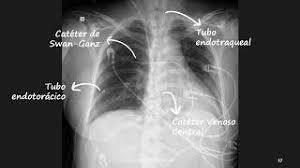

Catéter Swan-Ganz

El catéter Swan Ganz es un tipo de catéter central, usado para la monitorización hemodinámica invasiva en la aurícula derecha y la arteria pulmonar del paciente crítico. Tiene varias luces y dispositivos, a través de los cuales se pueden medir los diferentes parámetros a controlar como son gasto cardíaco, presión venosa central, presión de la arteria pulmonar, saturación venosa mixta, temperatura central, administración de medicación y extracción de muestras.

• Radiografía

Radiografía

Uso de esta técnica para apoyar el diagnóstico y detectar situaciones adversas como desplazamiento del TET y verificación de la posición de vías centrales, sondas de alimentación.